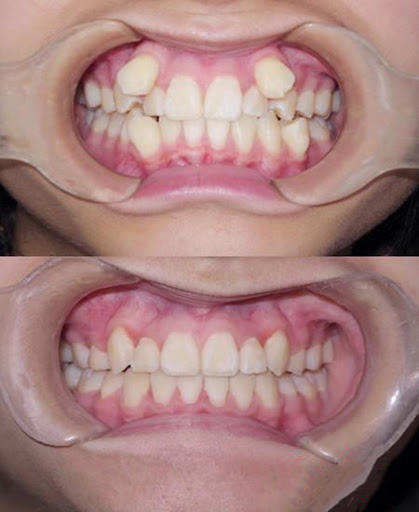

这两颗可怜的*牙虎**,因为被挤到牙列外,导致了两种效果:可爱和丑。如果*牙虎**长得好,就会起到助攻作用,让你就拥有可爱的权利;那*牙虎**长得不好,影响到颜值,是不是要拔掉呢?

孩子14岁前后,颌骨还在生长发育,随着颌骨的长大,在牙列的自行调整过程中,*牙虎**还有“归队”的可能。如果到了17岁*牙虎**还在原位不动,那时可去找口腔科医生诊治,将*牙虎**后面的那颗牙拔掉,在唇颊肌肉的协同压力作用下,有可能把*牙虎**“请回”到正常牙列中去。

而成年人牙颌骨已经相对固定,可以采取正畸治疗方法,如果仅仅是觉得*牙虎**不好看,可以采取牙齿贴面,损耗小,时间短,见效快。